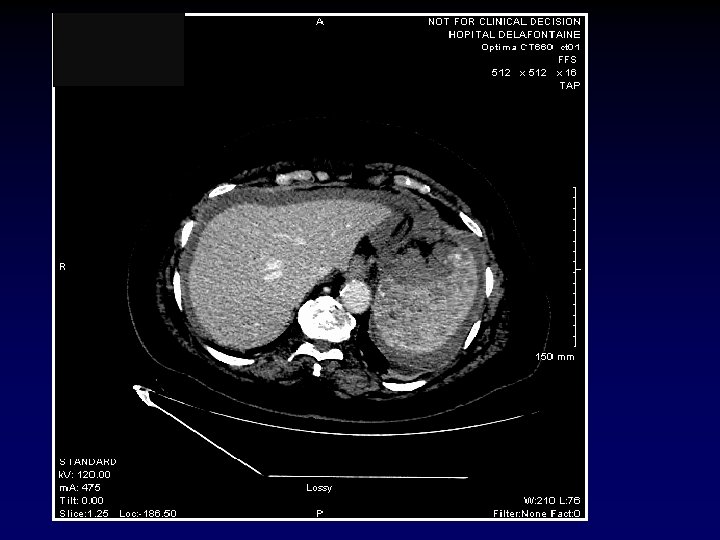

SCANNER ABDOMINAL AVEC IV le 07/01 Hématome avec aspect de fuite active au bord supéro-interne de la rate avec majoration de l’épanchement péritonéal et aspect de fuite active de contraste à deux niveaux Densité splénique hétérogène au temps portal prenant un aspect nodulaire